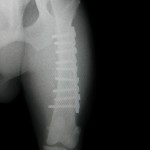

1例は2骨片の骨折です。

プレート・スクリューで固定でき、歩行も問題ありません。

(もう数ヶ月前に手術は終わっています)

整形外科はいかに適切なインプラントを用いて手術するかによって、

術後の状態も変わってきます。